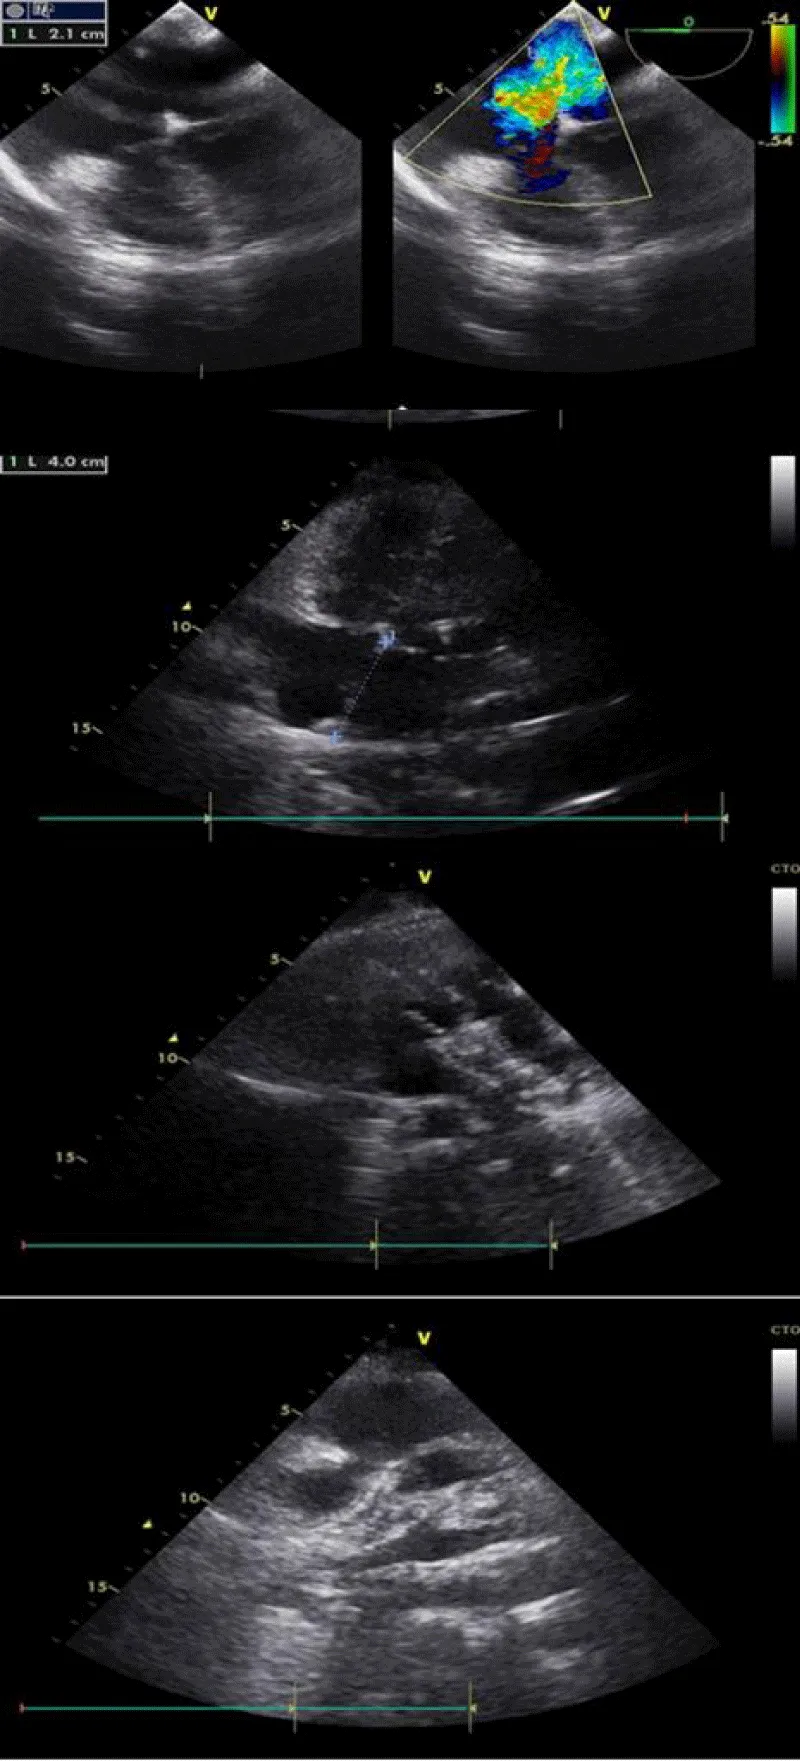

We started by crossing the ASD via the MPA and we positioned the 0.035’’ stiff guidewire in the upper then lower left pulmonary vein, however each time the angle with which the calibration balloon cross the ASD was unfavorable and brought the 0.035’’ wire back into the right atrium.

We decided then to put the wire in the aorta (through the ASD, then in the LA then LV and finally in the descending aorta as far as possible) in order to increase the support. From then on, the rest of the procedure became simple.

We reintroduced the calibration balloon giving a stretched ASD diameter of 23 mm (measurement by angiography and echocardiography TTE/TEE) fixing our choice on a 26 mm prosthesis which requires a septum height of 40 mm (26 + 2×7) that was exactly our patient’s septum height.

Then, we introduced the 12 Fr sheath from the internal jugular vein and prepared the prosthesis in its chamber as described earlier in this document.

The deployment and release of the prosthesis were done under angiographic and echocardiographic control (TTE/TEE).

For that, we started by putting the delivery system through the mitral valve in order to increase the support and stabilize the system, then we pushed the prosthesis till the end of its sheath and then we pulled back everything into the left atrium (to avoid trapping the prosthesis in the mitral cords) to deploy the distal disc, brought back into contact with the septum than the proximal disc to thus sandwich the septum between the two discs (Figure 3).

Figure 3: Procedure angiography.